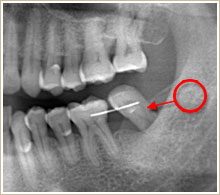

治療後のレントゲンです。赤丸の部位から移動しました。